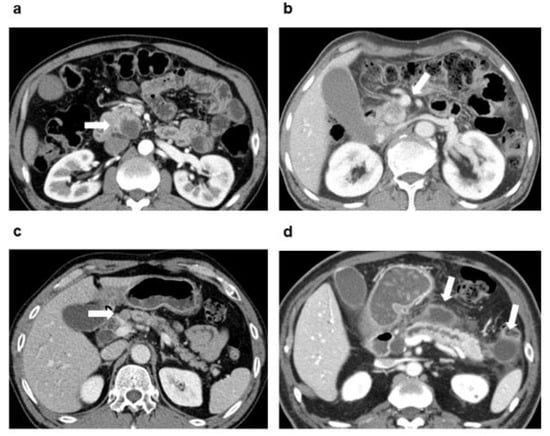

2.2. CT Imaging

2.3. Image Analysis

| Necrosis on CT | 1.64 | 0.97–2.79 | 0.066 | 2.42 | 1.39–4.21 | 0.002 |

| PV or SMV invasion on CT | 1.4 | 0.89–2.21 | 0.150 | 1.67 | 0.99–2.81 | 0.055 |

| Regional LN suspicious for metastasis on CT | 2.07 | 1.35–3.19 | 0.001 | 1.53 | 0.92–2.54 | 0.099 |

| Associated pancreatitis or pseudocyst on CT | 0.51 | 0.30–0.86 | 0.013 | 0.54 | 0.30–0.98 | 0.041 |